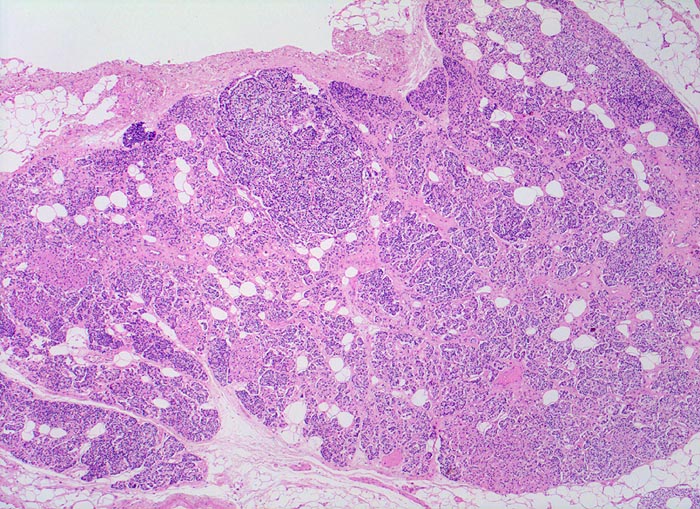

normale Nebenschilddrüse

Nebenschilddrüse

Bei Erwachsenen beträgt die Menge des stromalen Fettgewebes zwischen 10 und 30 Prozent (hier etwa 10%). Die Nebenschilddrüsen ist umgeben von einer schmalen bindegewebigen Kapsel. Ausgehend von der Kapsel ziehen schmale fibröse Trabekel in das Parenchym. Die oxyphilen Zellen bilden kleine rosarote Knoten innerhalb der grösseren Masse basophiler Hauptzellen.

5mm lange braunrote Drüse von 30mg.

Eine Nebenschilddrüse wiegt beim Mann durchschnittlich 31.1mg bei der Frau 29.8mg. Die beiden unteren Drüsen sind grösser als die oberen.